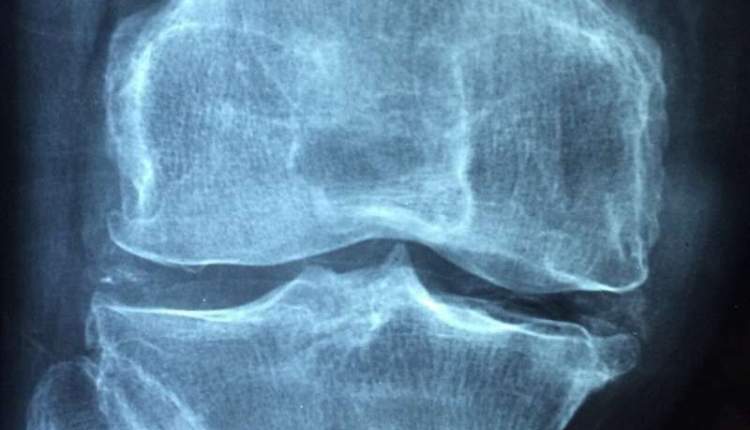

آرتریت (التهاب مفاصل) به التهاب دردناک در ناحیه مفاصل گفته می‌شود و یکی از بزرگترین معضلاتی است که افراد به مرور زمان و با گذشت سن با آن مواجه می‌شوند. استئوآرتریت (آرتروز)، آرتریت روماتویید، آرتریت عفونی، ورم مفاصل پسوریاتیک و نقرس، پنج گروه عمده آرتریت هستند. آرتروز شایع‌ترین نوع آرتریت است. این التهاب دردناک سبب تورم و اختلال حرکت مفاصل می‌شود و معمولا در ناحیه دست، زانو، لگن و ستون مهره‌ها بیشتر است. سه عامل اضافه وزن، سن و آسیب دیدگی مفاصل، مهمترین دلیل بروز آرتروز هستند.